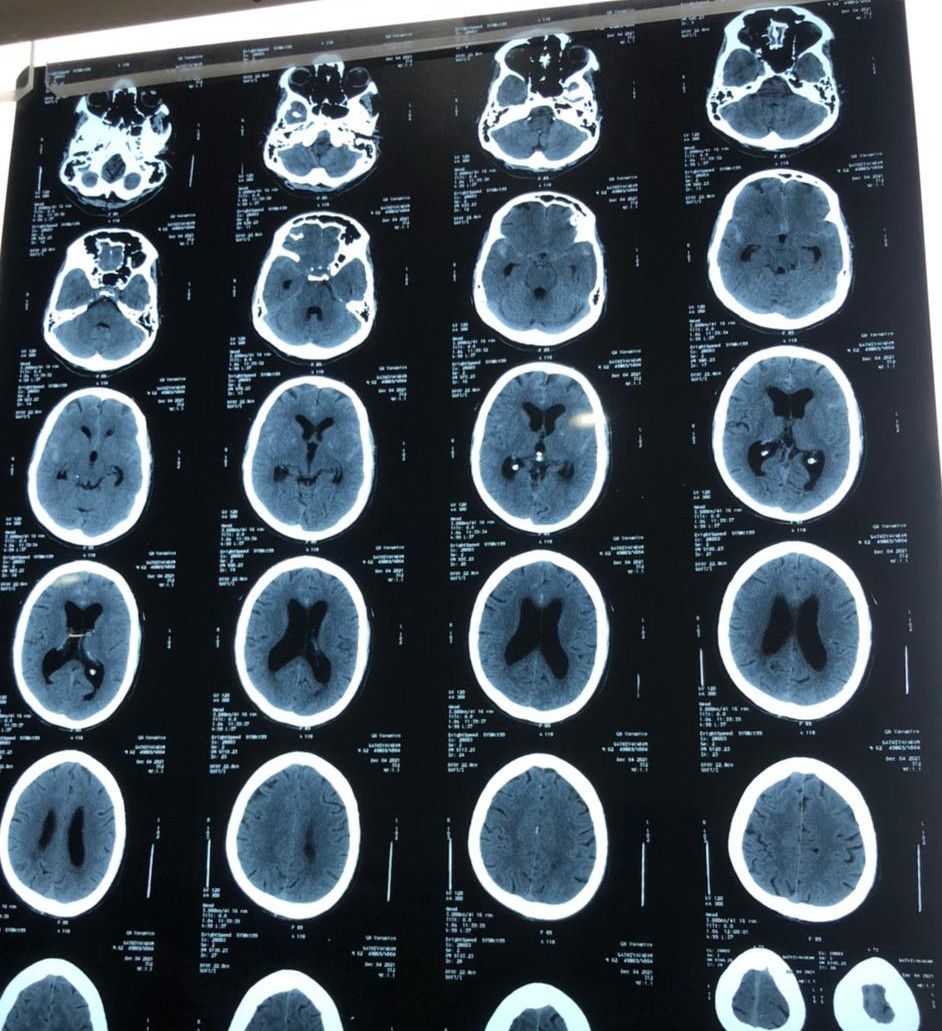

Hydrocephalus due to subarachnoid haemorrhage

Communicating type hydrocephalus